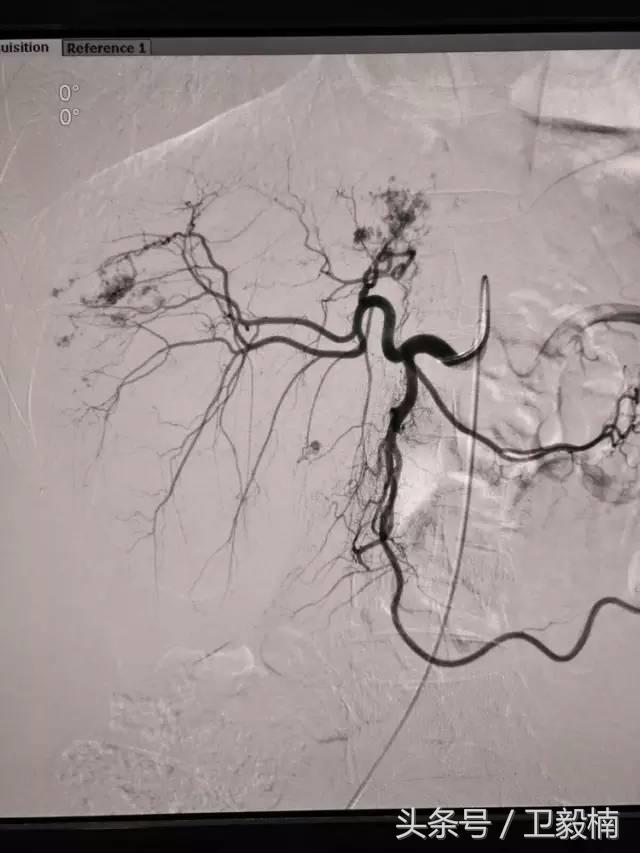

2、经导管血管栓塞法(Transcatheter embolization)

经原血管造影的导管或特制的导管,将栓塞物送至靶血管内,一是治疗内出血如外伤性脏器出血、溃疡病、肿瘤或原因未明的脏器出血。另一是用栓塞法治疗肿瘤,因肿瘤循环部分或全部被栓塞物阻断,以达控制肿瘤之生长,或作为手术切除的一种治疗手段;亦可用于非手术脏器切除,例如注射栓塞物质于脾动脉分支内,即部分性脾栓塞,以治疗脾功亢进,同时不影响脾脏的免疫功能。

常用的栓塞物质如自体血凝块、明胶海绵、无水酒精、聚乙烯醇、液体硅酮、不锈钢圈、金属或塑料小球及中药白芨等。

(1)选择性肿瘤供血动脉灌注化疗+栓塞治疗恶性肿瘤。

(3)应用栓塞术治疗海绵状血管瘤,蔓状血管瘤,子宫肌瘤,骨肉瘤,鼻咽部纤维血管瘤等。